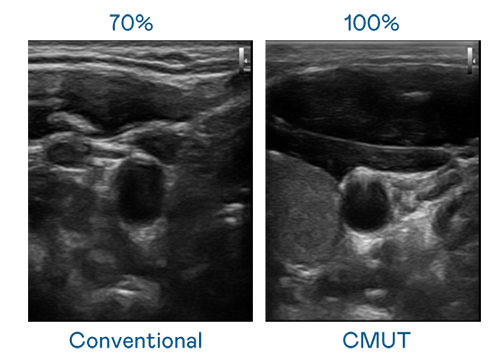

CMUT 技术是一种用电容式微机电元件来产生超音波讯号的技术。与传统 PZT 压电式技术相比,CMUT 频宽增加 30%,更宽频的超音波讯号让影像解析度大幅提升,是实现高影像品质医疗超音波扫描、促进精准医疗发展的关键技术。

大频宽带来超清晰影像

超音波影像的解析度高低,首先取决于探头能发出的讯号频宽。BG真人 CMUT 可提供高清晰的超音波讯号,提供高频宽、高灵敏度、影像纹理细节更高的超音波影像,协助医护人员缩短影像判读时间及利用精准的医疗影像进行诊断。